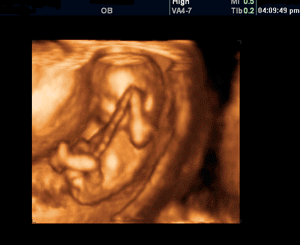

В современной медицине появилось трёхмерное УЗИ. Оно становится очень популярным и желанным методом исследования у будущих родителей. Изображение при таком УЗИ очень объёмно и гораздо нагляднее, чем плоская картинка.

Во время проведения УЗИ вы сможете первый раз увидеть своего будущего ребёнка. Я уверена, что эта самая первая встреча запомниться вам навсегда.